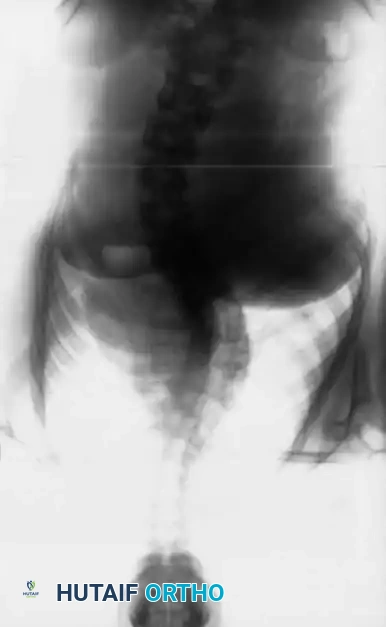

Anterior instrumentation and fusion have historically been a well-accepted, powerful procedure for specific curve patterns, particularly thoracolumbar and lumbar curves.

Indications and Curve Selection

The ideal candidate for an anterior approach is a patient with a Lenke Type 4 curve pattern, where the thoracolumbar or lumbar curve is the primary structural component, and the main thoracic or proximal thoracic curves are nonstructural and highly flexible.

Anterior instrumentation provides unparalleled derotation and correction of the deformity in the coronal plane due to the complete excision of the intervertebral discs and anterior longitudinal ligament, which are the primary anterior tethers.